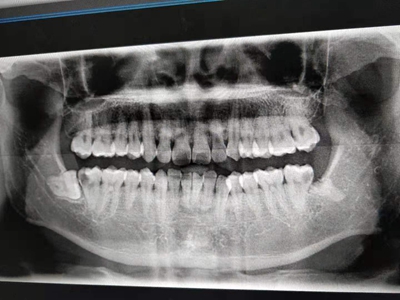

阻生牙是指由于邻牙、骨或软组织的阻碍而只能部分萌出或完全不能萌出,且以后也不能萌出的牙。引起牙阻生的成因,主要是由于颌骨缺乏足够的空间容纳全部恒牙。常见的阻生牙为下颌第三磨牙、上颌第三磨牙及上颌尖牙。

阻生牙主要原因是随着人类的进化,颌骨的退化与牙量的退化不一致,导致骨量相对小于牙量,颌骨缺乏足够的空间容纳全部恒牙。

对于阻生牙的处置需要首先明确阻生牙齿发育情况是否正常,对于由于早期外伤或其他原因造成发育异常,如牙根弯曲、短根等情况的阻生牙,还应根据患者的综合情况,决定牙齿是否保留。

发育正常的牙齿同时正畸治疗又不需要进行拔牙矫治,通常需要对阻生牙进行牵引治疗,引导进入牙弓,而对于发育异常的阻生牙加之正畸治疗需要进行拔牙矫治,通常可以考虑将阻生牙拔除,而避免再拔发育正常的前磨牙,即降低了正畸治疗的难度及不确定性,又保留了相对正常的牙齿。